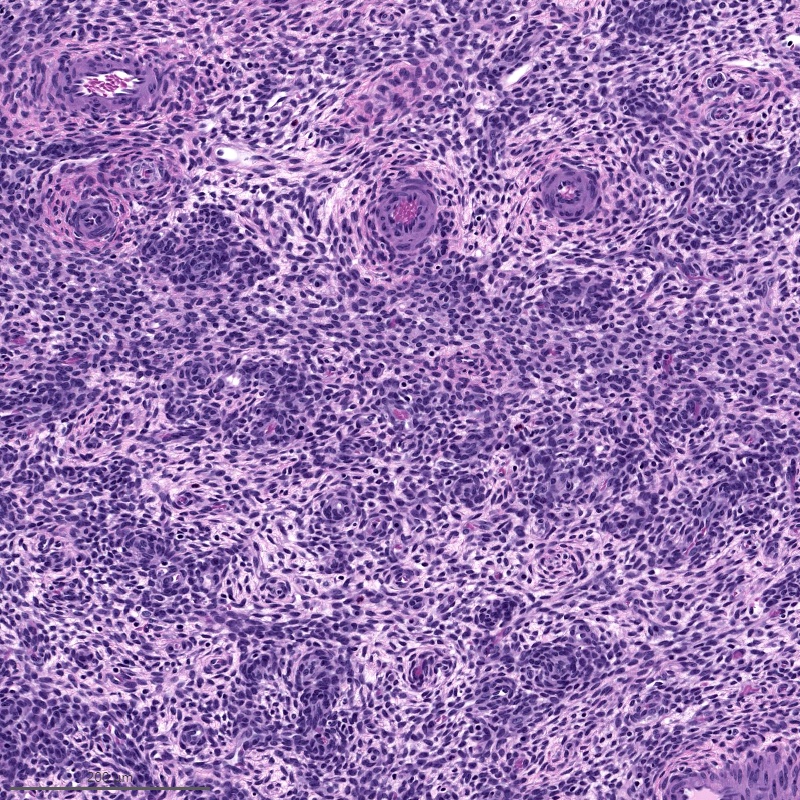

Microscopic (histologic) description

- Irregular cellular islands, forming permeative tongue-like pattern of myometrial invasion with frequent vascular invasion

- Monotonous oval to spindle cells with minimal cytologic atypia, vesicular chromatin and scant cytoplasm

- Mitotic count is usually low (< 5/10 high power fields), necrosis is usually absent

- Tumor cells may whorl around delicate arteriolar type vessels, reminiscent of proliferative phase endometrial stroma

- May have admixed collagen bands / plaques and foamy histiocytes

- May have smooth muscle differentiation, particularly in a starburst morphology, with collagen bands radiating towards the periphery of the nodule

- Other reported types of differentiation: fibromyxoid / fibrous, sex cord-like, epithelioid, rhabdoid, endometrioid glands, pseudopapillae, clear cells, bizarre cells, adipose tissue (Mod Pathol 2016;29:S92)

Microscopic (histologic) images

Contributed by Elizabeth Kertowidjojo, M.D., Ph.D., M.P.H. and Ayse Ayhan, M.D., Ph.D.